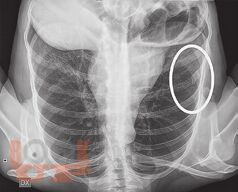

В книге рассмотрены вопросы применения методов визуализации при проведении судебно-медицинской экспертизы живых лиц и трупов. Особое внимание уделено судебно-медицинскому значению рентгенографии, посмертной компьютерной томографии и посмертной магнитно-резонансной томографии. Описаны возможности посмертной ангиографии для визуализации повреждений кровеносных сосудов. Авторы критически характеризуют преимущества и недостатки так называемой виртуальной аутопсии.